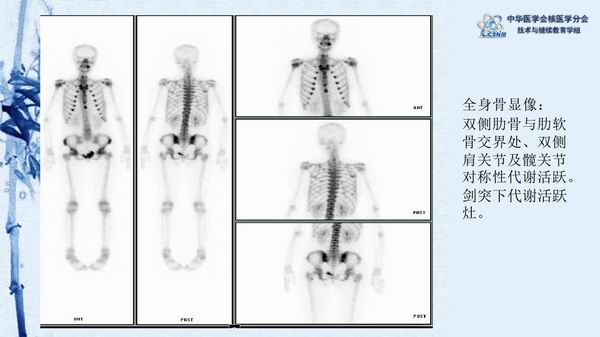

讲座15:复发性多软骨炎-张卫方